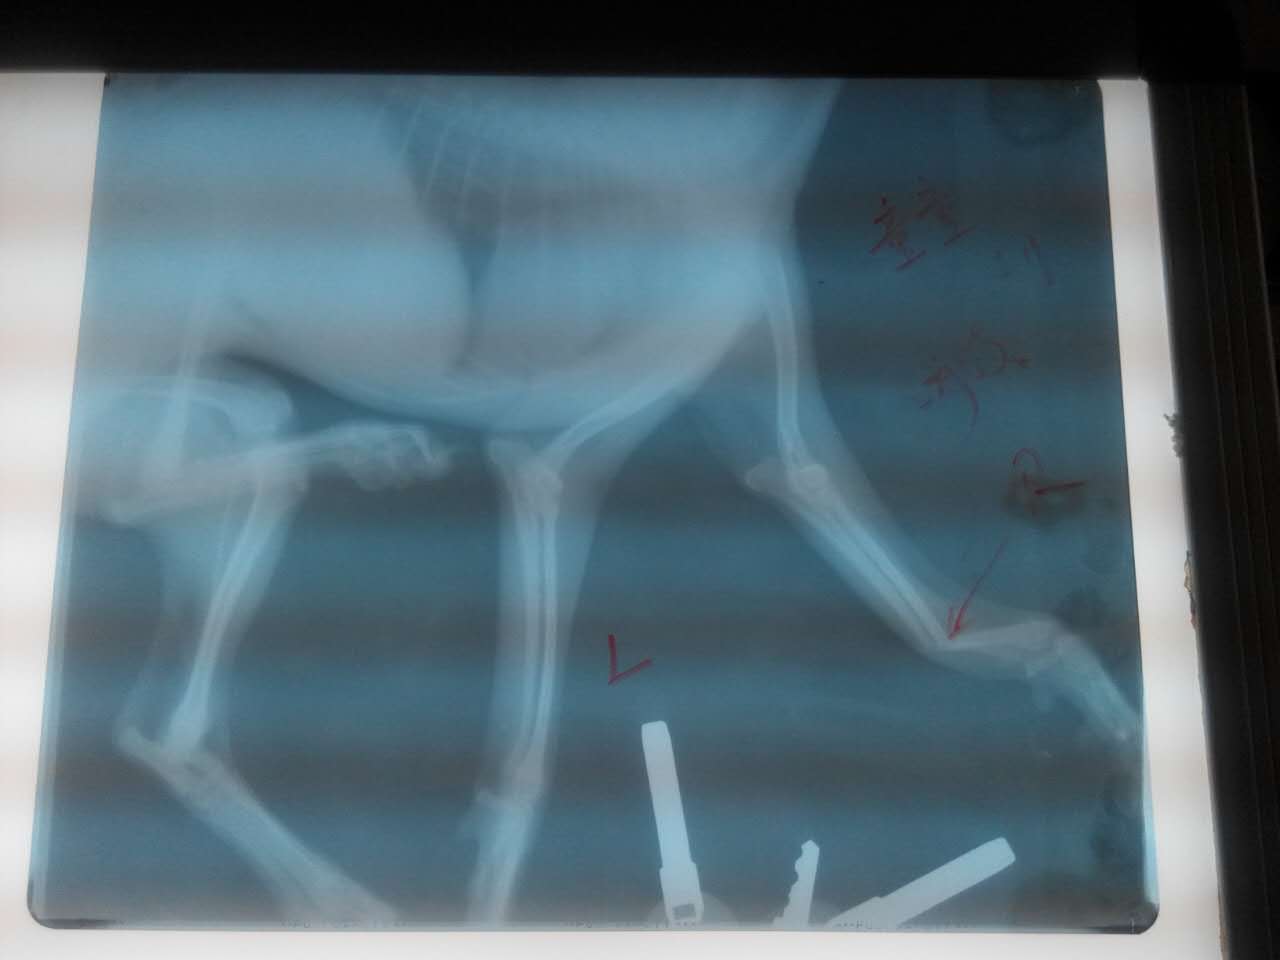

洛龍區元華國際,母泰迪犬童童從高處墜落己四天,X光片顯示右前肢前臂骨遠端完全骨折,且呈100度背角移位。

精心治療中

經整變固定,35天后痊愈。